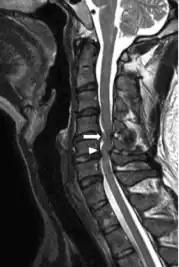

Image indicates C5–C6 with severe spinal cord compression (and large disc herniation at C4–C5 ) -

Compressive myelopathy at the C6-C7 level due to disc protrussion